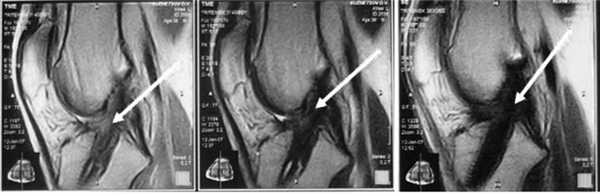

Кроме того, после операции, помимо клинического обследования, мы выполняли МРТ для еще большей объективизации результатов аутопластики ПКС коленного сустава. Контрольная МРТ проводилась через год после аутопластики ПКС (рис. 4).

Рис. 4. МРТ-изображение трансплантата ПКС в разных срезах через 1 год после операции (указано стрелками). Трансплантат выглядит структурным, гомогенным и напряженным.

В последующем при обращении пациентов в клинику проводился МРТ-контроль в более поздние сроки. МРТ-контроль позволял определить плотность, структуру, напряжение трансплантата по наличию четкого контура, признаки его разрыхленности или повреждения (рис. 5 и 6).